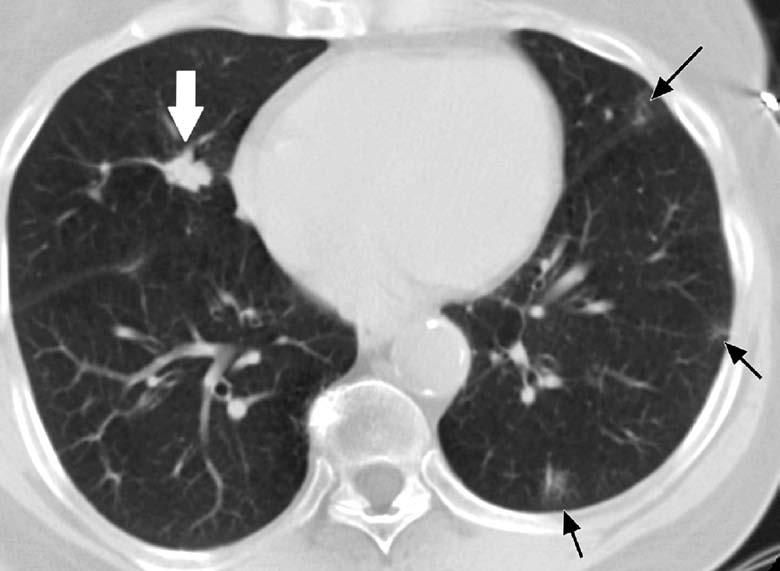

In patients with RA, nodules that do not regress should be evaluated in a manner similar to that for solitary or multiple pulmonary nodules in other patients (Figure 2). The differential diagnosis includes infection, malignancy, and other inflammatory disease (Table). In particular, fungal infection may be seen in patients who receive immunosuppressive agents to control their joint symptoms, and the reactivation of latent tuberculosis has been reported with the use of the newer anti–TNF-α agents.46

Figure 2 – A lung nodule was detected in a 63-year-old woman who had a long-standing history of rheumatoid arthritis and who presented with dry cough. Abnormal chest radiographic findings prompted a CT scan of the chest, which showed a 1-cm nodule with irregular margins in the right middle lobe (white arrow). Peripheral, patchy, ground-glass nodular densities consistent with underlying interstitial lung disease are also seen (black arrows). At surgery, a 1-cm squamous cell carcinoma, T1N0, was resected. The nonneoplastic lung revealed follicular bronchiolitis.

Smoking is associated with the development of rheumatoid nodules.47 Because many patients with RA have a strong history of smoking, close attention should be paid to the follow-up and evaluation of lung nodules. Depending on the clinical situation, serial radiographic follow-up, needle biopsy, or resection may be considered. However, the documentation of one pathologically confirmed rheumatoid nodule does not ensure the benign nature of other nodules in the same patient.48